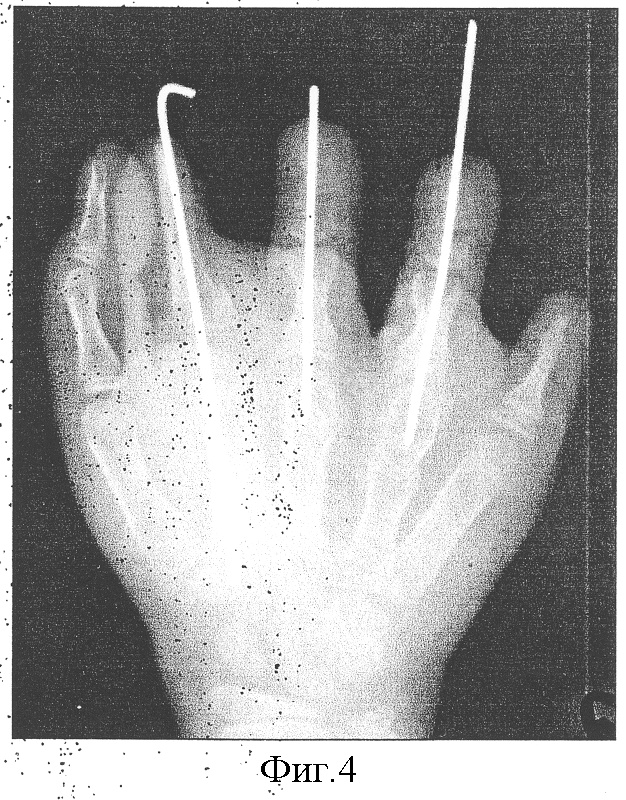

Больная Р., 7 лет, с диагнозом врожденная брахидактилия правой кисти, находилась на лечении в отделении реконструктивной микрохирургии и хирургии кисти ФГУ НИДОИ им. Г.И.Турнера. Первым этапом выполнено восстановление 3-4 пальцев кисти путем микрохирургической пересадки 2 пальцев обеих стоп. Далее произведена свободная костная пластика основной фаланги 2 пальца кисти губчато-кортикальным аутотрансплантатом из гребня подвздошной кости. Через 6 месяцев после операции лизис костного трансплантата, в связи с чем выполнена костная пластика кровоснабжаемым трансплантатом из 2 пястной кости правой кисти. Одновременно с этим устранена клинодактилия 3-4 пальцев. Через 1 год после операции – полное восстановление косметического вида и функции кисти.

Фиг.4 – рентгенограмма кисти на этапе лечения (восстановление 2 пальца кисти путем пластики кровоснабжаемым трансплантатом из 2 пястной кости, а также устранение клинодактилии 3-4 пальцев кисти, ранее пересаженных со стопы).